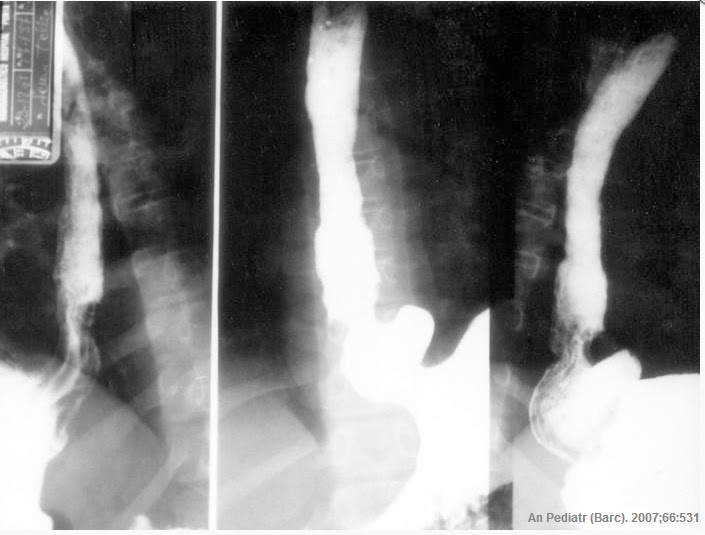

Esófago, hernia hiatal, y acalasia

Optativa DDI 2014: Caso discutido em 26/03 - Rx Contrastado